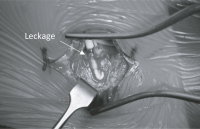

Abbildung 2: Intraoperative Darstellung des spinalen Katheters.

Keywords:

intrathekale Baclofentherapie

,

Operationssitus

spinaler Katheter